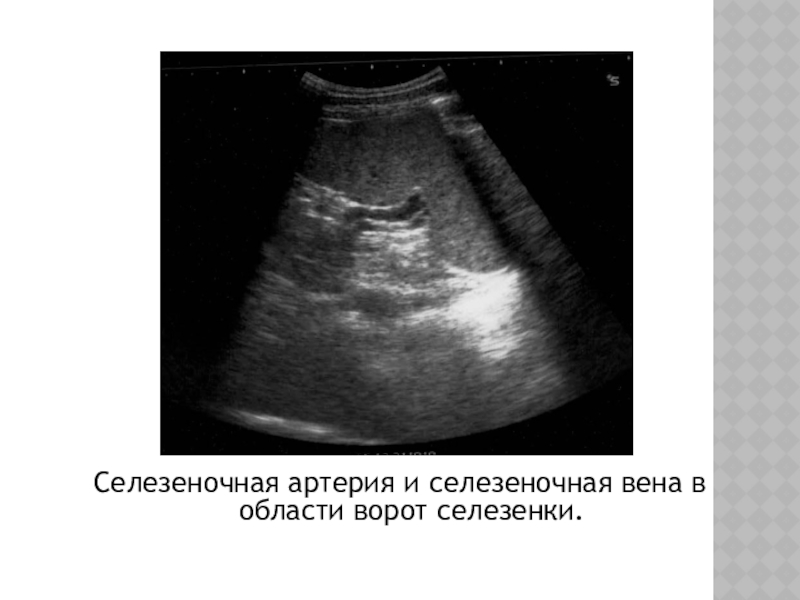

Слайд 5Селезеночная артерия и селезеночная вена в области ворот селезенки.

Селезеночная артерия и селезеночная вена в области ворот селезенки.